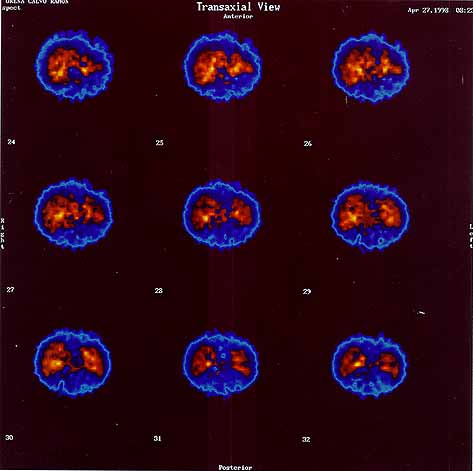

fig. 3

Figura 3. Gammagrafía.

fig. 4

Figura 4. Gammagrafía